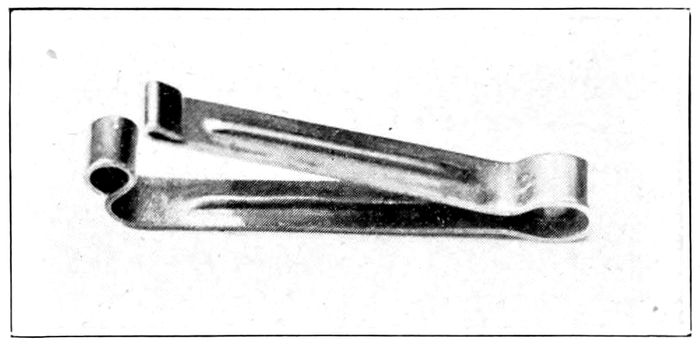

The Pettit cord clamp |

268 |